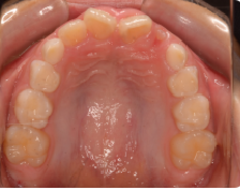

歯は削れば削るほど、もろくなります。歯の表面のエナメル質に無数のひびが入ったり、インレー(歯の詰め物)

(虫歯よりもかなり大きく削る)を装着すると、くさびのような働きをして、歯が割れてしまう事があります。

一時治ったと思っても、長い目でみると歯そのものの寿命を短くしてしまいます。